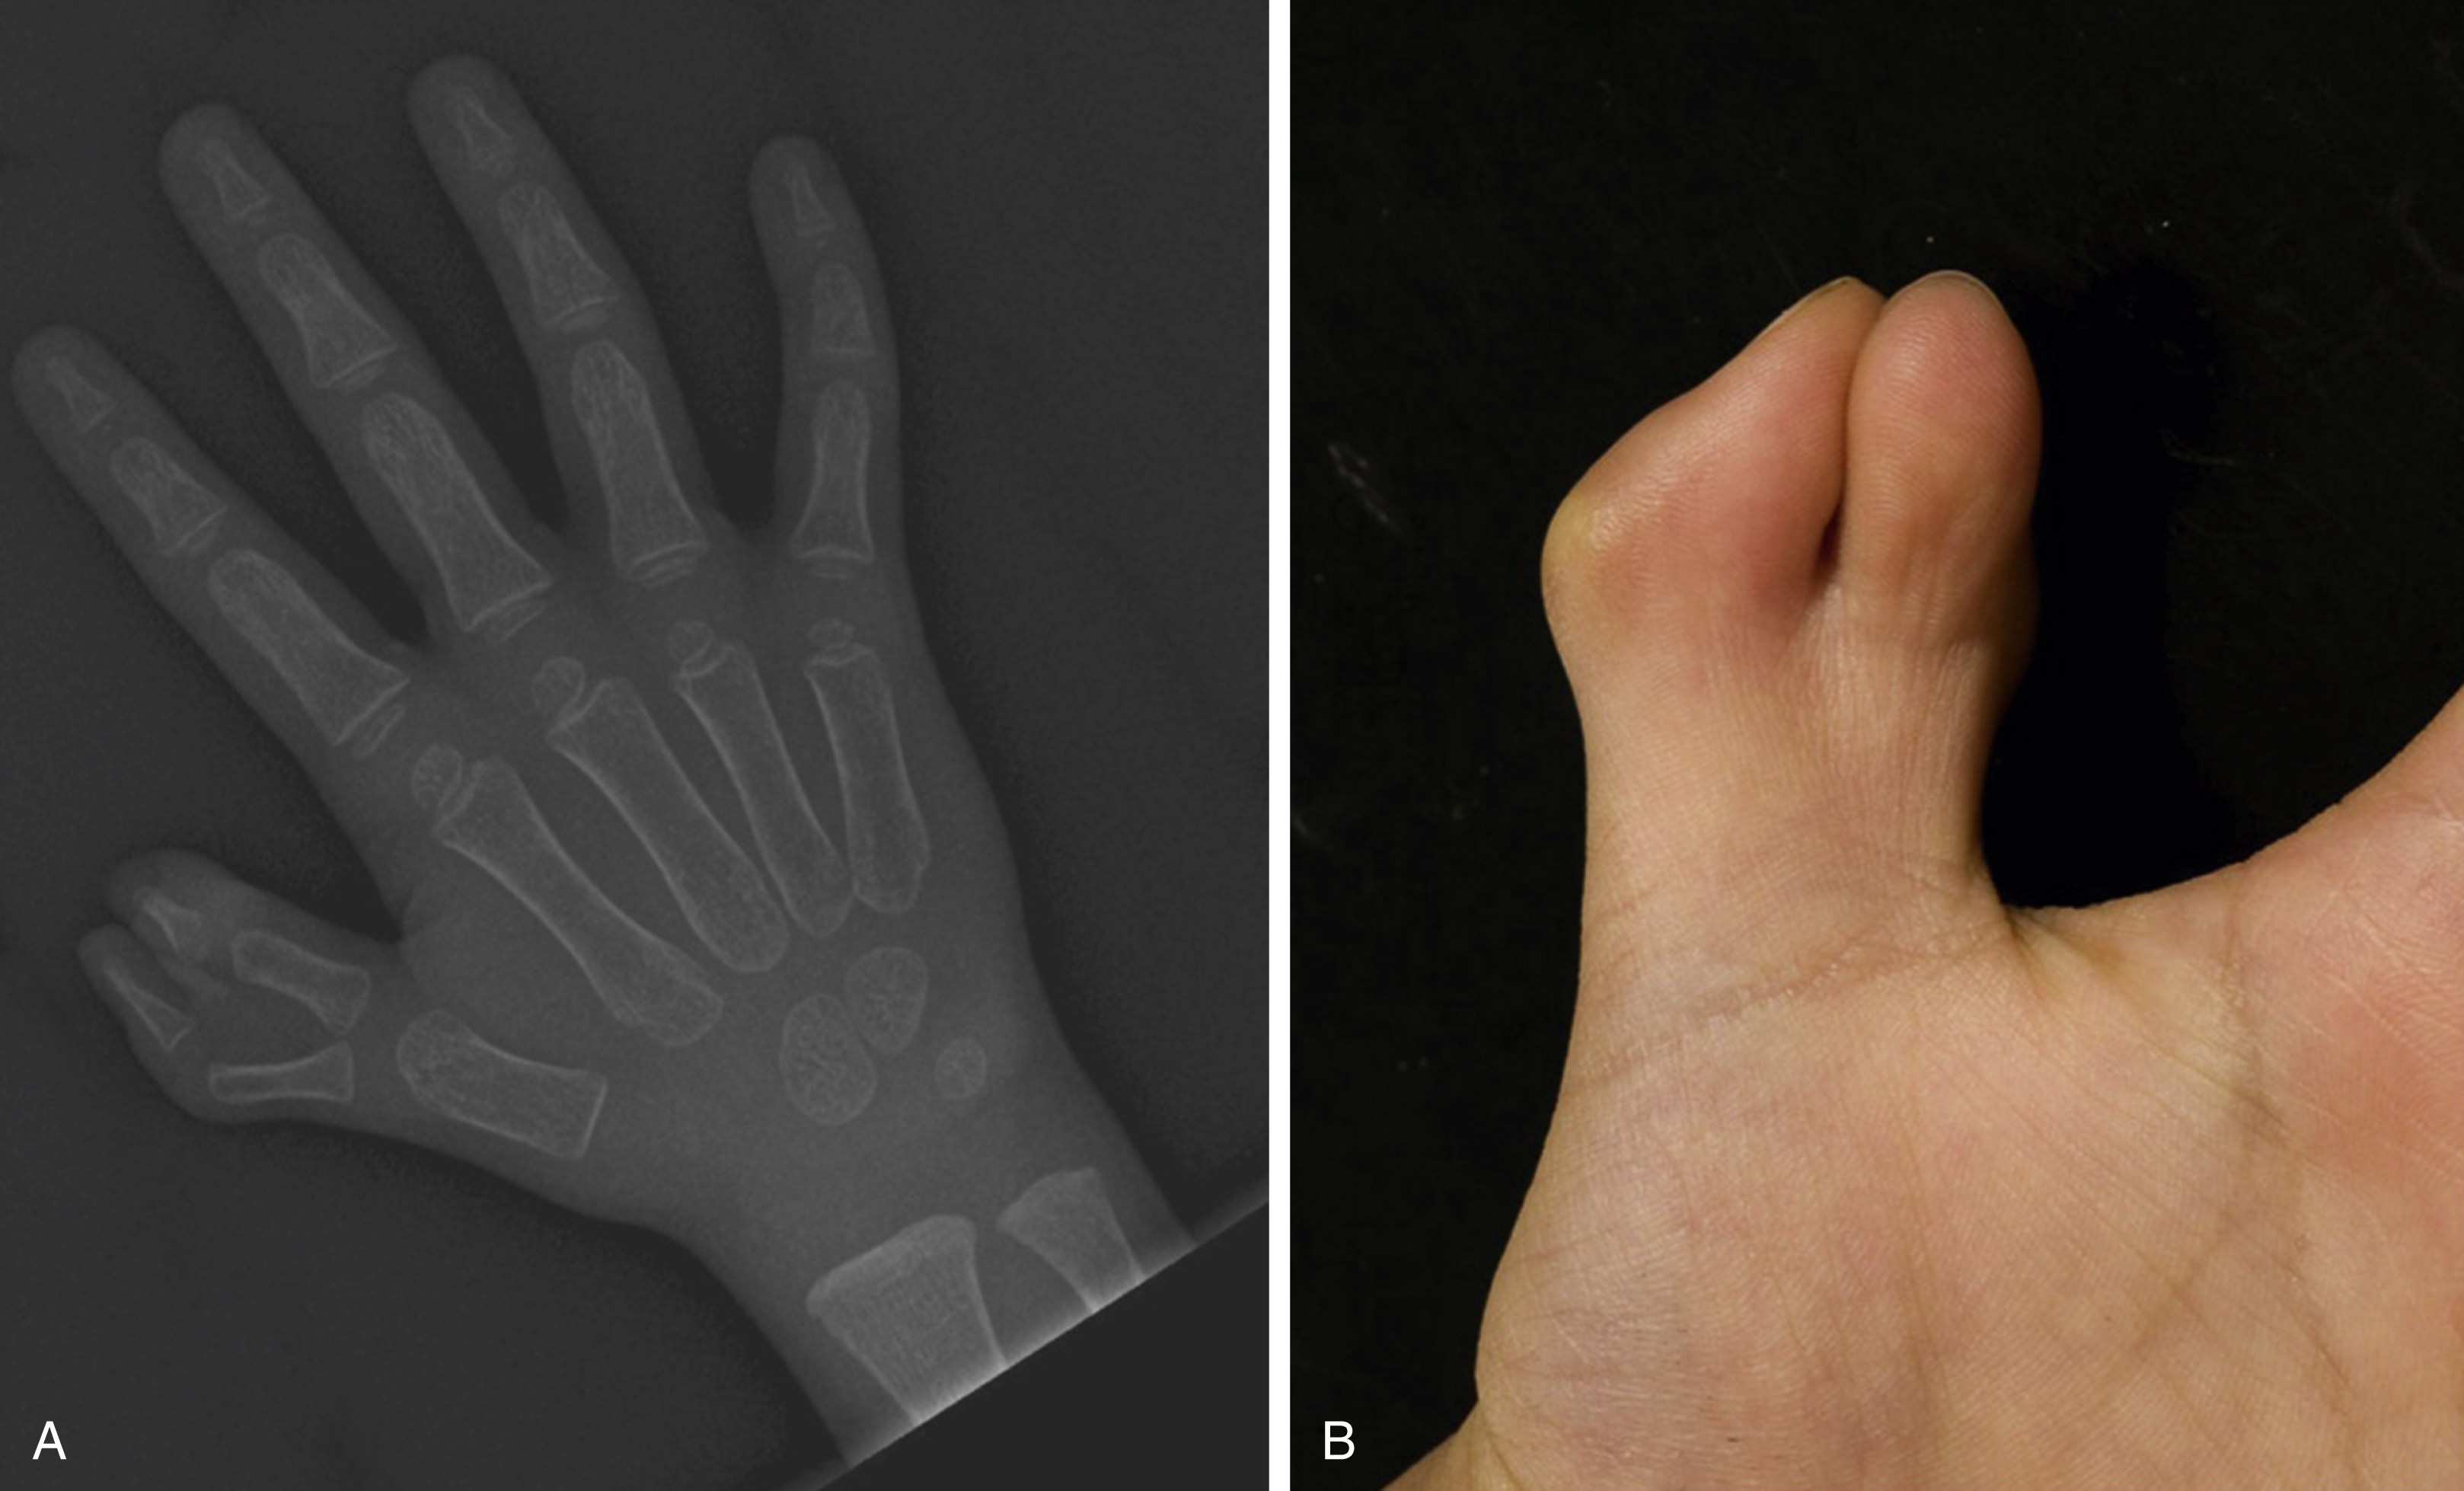

Syndactyly

A normal web ends at the midproximal phalanx on the volar side and an abnormal continuation beyond this level is termed syndactyly (Greek syn = together, dactylos = digit/finger). Syndactyly is the commonest congenital hand abnormality, with an incidence of 1 in 1000 live births. It is more common in Caucasians than Africans and affects males more than females (46%–84%). It is familial in 15%–40% and can be unilateral or bilateral (25%–50%). Syndactyly may affect the fingers and/or toes and most commonly presents as an incomplete second web syndactyly in the foot. In the hand, the third web is most frequently involved (50%) (see Fig. 45.2A, B ), followed by the fourth (30%), second (15%), and first (5%) %). A failure of apoptosis or programmed cell death, a process mediated by BMP-4 (bone morphogenic protein), is thought responsible during digit separation from day 41–53.

Syndactyly is classified as follows ( Fig. 45.2 ):

Incomplete or complete (extending to the distal phalanx)

Simple (soft tissue only) or complex (with bony synostosis)

Complicated (a haphazard arrangement of bones with loss of normal ray patterning)

Acrosyndactyly (fusion of digits distally, from the Greek acro meaning “tip,” with proximal fenestrations commonly associated with constriction ring syndrome).

Inspect the syndactylized digits. With complete syndactyly, the nails can be fused with an inward rotation of the digits, which eludes to the presence of a complex distal bony union ( Fig. 45.2C ). The degree of skeletal disruption within a syndactyly tends to parallel the degree of soft tissue abnormality, including that of tendons and digital neurovasculature structures. It is important to examine for the presence of digital creases, which provides valuable information about the passive and active joint range of motions, which may also be abnormal. The status of the joints pre-separation must be established to ensure adequate counseling of patients and their families with regard to the postoperative motion and function. Often a child and family will opt for the correct complement of digital number over function in equivocal cases.

In complicated syndactyly there is more than just a bony synostosis. Often there is a haphazard arrangement including extra skeletal elements concealed within a digit with associated fusions, rudimentary bones, missing bones, abnormal joints, and sometimes cross bones, which can span several rays ( Fig. 45.2D ). It can be uncertain which bones best match with which digits. In acrosyndactyly, there is a complex syndactyly characterized by fusion of the bone distally but not proximally with often fenestrations or sinuses proximally ( Fig. 45.2E ). This is discussed later under Constriction Ring Syndrome (CRS).